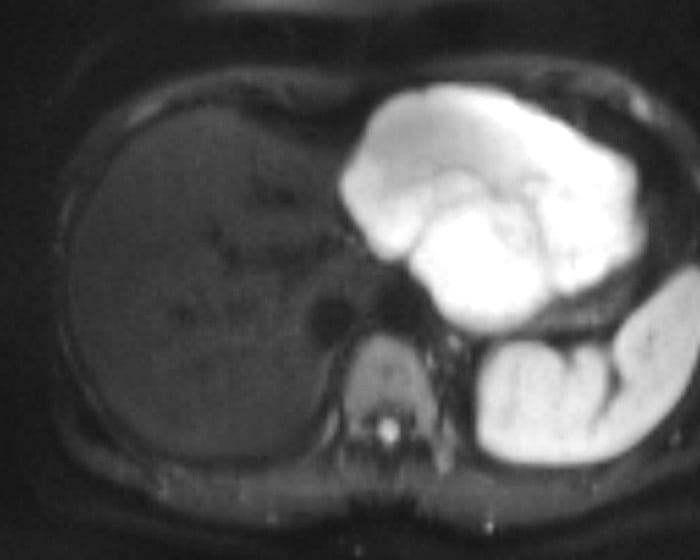

U máu gan

» Thông tin: Nữ giới – 47 tuổi.

» Lâm sàng: Đau thượng vị.